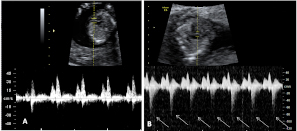

Doppler pulsado en la válvula tricúspide. Registro normal (imagen A) y registro con insuficiencia (imagen B con flechas).